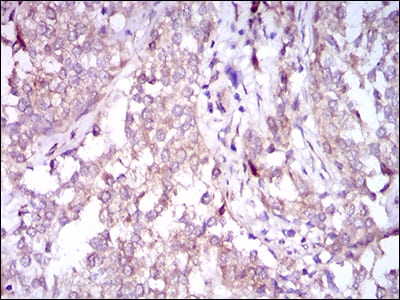

Immunohistochemical analysis of paraffin-embedded human cervical cancer tissues using SQSTM1 mouse mAb with DAB staining.

-

Immunohistochemical analysis of paraffin-embedded human bladder cancer tissues using SQSTM1 mouse mAb with DAB staining.